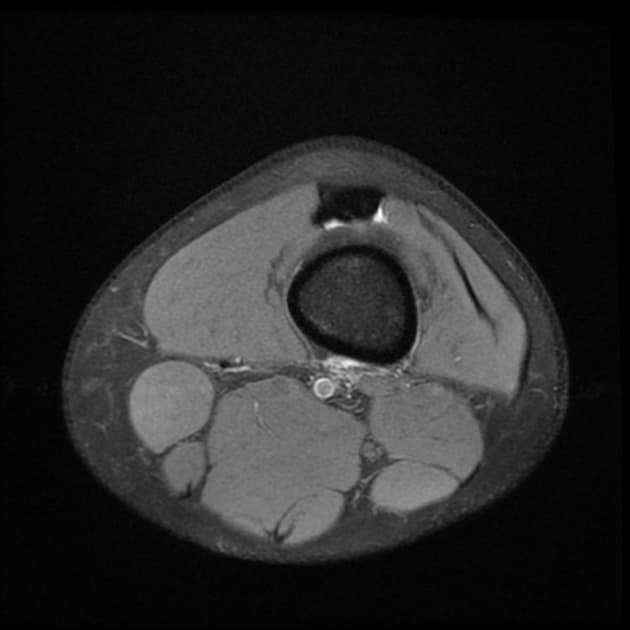

Axial PD fat sat

- Ghi nhận tổn thương dập (contusion) ở lồi cầu ngoài của xương chày.

- Ghi nhận lượng dịch khớp vừa (moderate amount of joint effusion).

- Thấy tín hiệu dịch bao quanh dây chằng bên ngoài, gợi ý căng giãn dây chằng (sprain).

Tháp mạc gối lật ngược là một dạng đặc biệt của rách dạng xô, thường gặp ở sụn chêm bên. Tình trạng này xảy ra khi một vết rách dọc dọc cho phép một mảnh lớn của sụn chêm—thường là thân và sừng sau—di lệch về phía trước và vào trong vào khe gian lồi cầu. Sự di lệch này dẫn đến 'dấu hiệu sụn chêm ảo', khi giường sụn chêm nguyên bản trông trống rỗng trên hình ảnh cắt dọc. Mảnh sụn di lệch nằm kề sừng trước, tạo thành 'dấu hiệu tam giác kép'—hai cấu trúc hình tam giác riêng biệt có cường độ tín hiệu thấp, đại diện cho sừng trước bình thường và mảnh sụn bị lật. Các phát hiện đi kèm như tổn thương dập xương, dịch khớp và căng giãn dây chằng thường gặp do cơ chế chấn thương. Việc nhận diện sớm trên cộng hưởng từ rất quan trọng để lên kế hoạch phẫu thuật, vì tổn thương này thường cần được giảm chỉnh và sửa chữa nội soi.